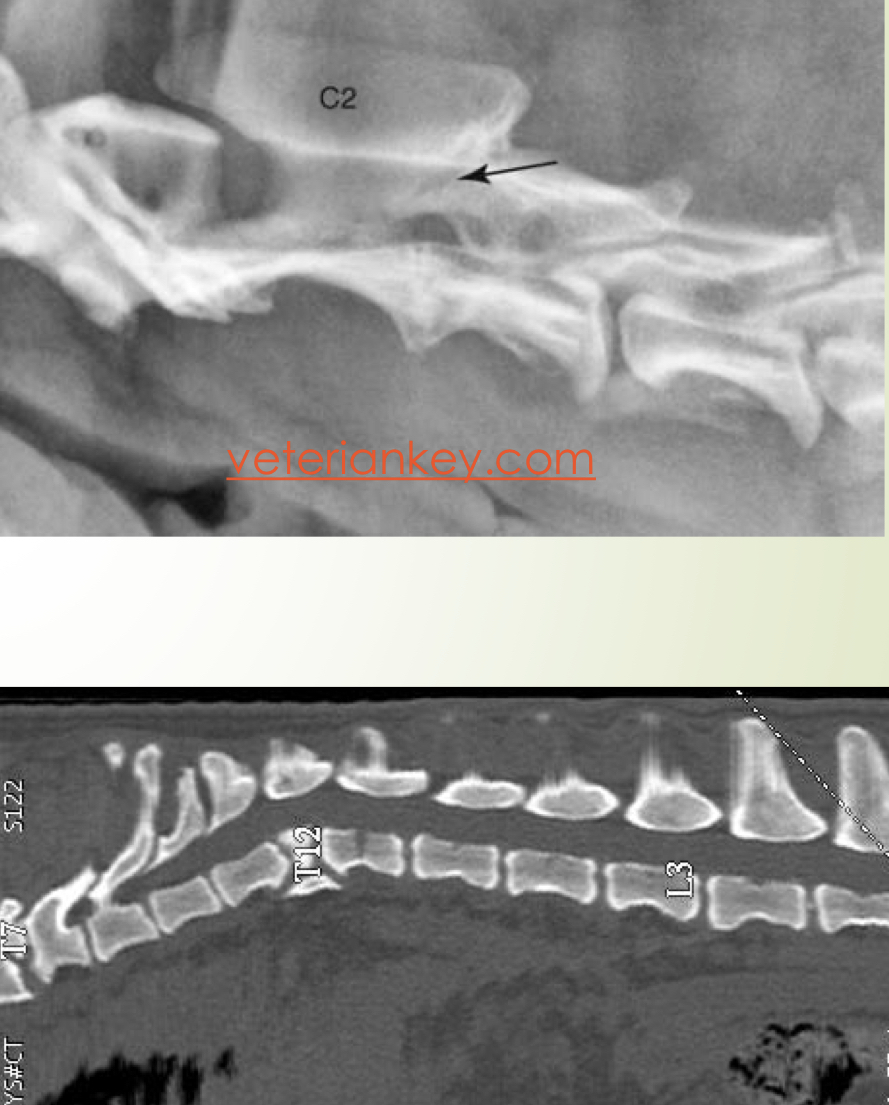

Anormalidades congénitas

Anormalidades vertebrales :

* Hemivértebra (braquicefalicos)

* Fusión vertebral

Subluxación atlantoaxial

Espina bifida

La mayoría de las veces no dan signos clinicos →Para confirmar que son la causa de los déficits : mielografia, mielotac o RM

Fallo núcleo osificación

A

Forma de cuña

Tipo :

* Lateral : escoliosis

* Dorsal : cifosis

* Ventral : lordosis